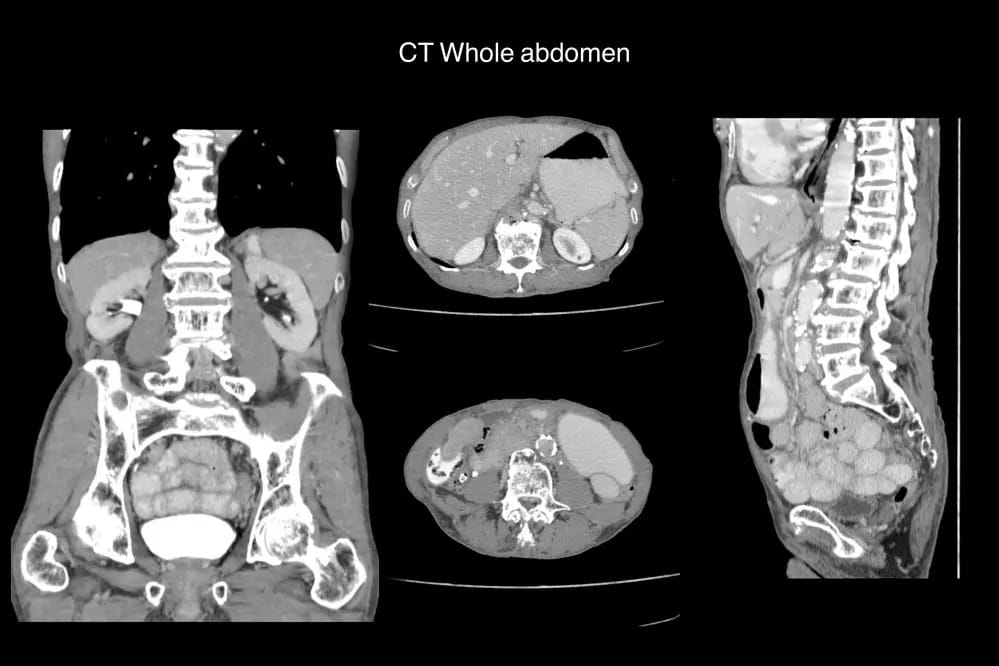

Диагностика причин болезненных ощущений селезенки основана на оценке ее размера, параметров гемодинамики, истории травмы или других заболеваний и других сопутствующих симптомов. Пальпация нижней границы селезенки может помочь оценить степень увеличения.

Врач может подтвердить проблемы c селезенкой на основании одного или нескольких из этих исследований:

- Анализы крови, чтобы проверить количество эритроцитов, лейкоцитов и тромбоцитов

- Ультразвуковая или компьютерная томография (КТ) для определения размера органа

- Магнитно-резонансная томография (МРТ) для отслеживания кровотока через селезенку.

Для постановки диагноза обязательно назначаются исследования с применением УЗИ, МРТ, КТ. На последних стадиях заболевания можно наблюдать гибель больших участков или всех селезеночных тканей. Патология распространена между мужчин и женщин, средний возраст которых составляет около 65 лет.

- Рентген — позволяет увидеть увеличение размеров селезенки, желчного пузыря, желудка, надпочечника, почки. Перед процедурой в брюшную полость пациента вводится кислород для улучшения информативности исследования.

- Ультразвуковое исследование органов брюшной полости.